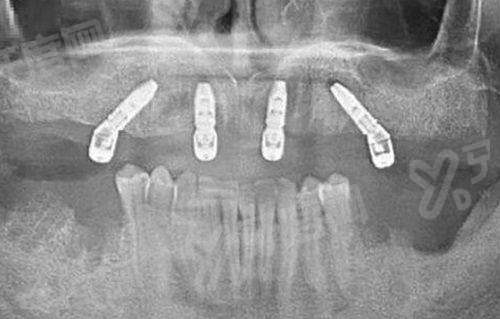

(二)特色技术:种植牙/矫正方案个性化

上海中博惠众口腔医院在种植牙方面,上海中博惠众口腔医院是提供多种品牌选择,从性价比高的韩国登腾到进口的德国ICX,每个品牌都有不同的适应症。比如韩国登腾种植牙适合预算有限但追求稳固性的患者,3980元起就能实现牙齿修复;美国皓圣种植牙生物相容性好,适合骨量较少的人群,7800元起;德国ICX种植体骨结合率高,能长期使用,8980元起。矫正牙齿也分年龄和需求,青少年用国产金属托槽正畸(9999元起)快速排齐,成年人喜欢隐形矫正,时代天使28000元起、隐适美38000元起,都是经过认证的隐形牙套品牌,戴起来美观又舒适。